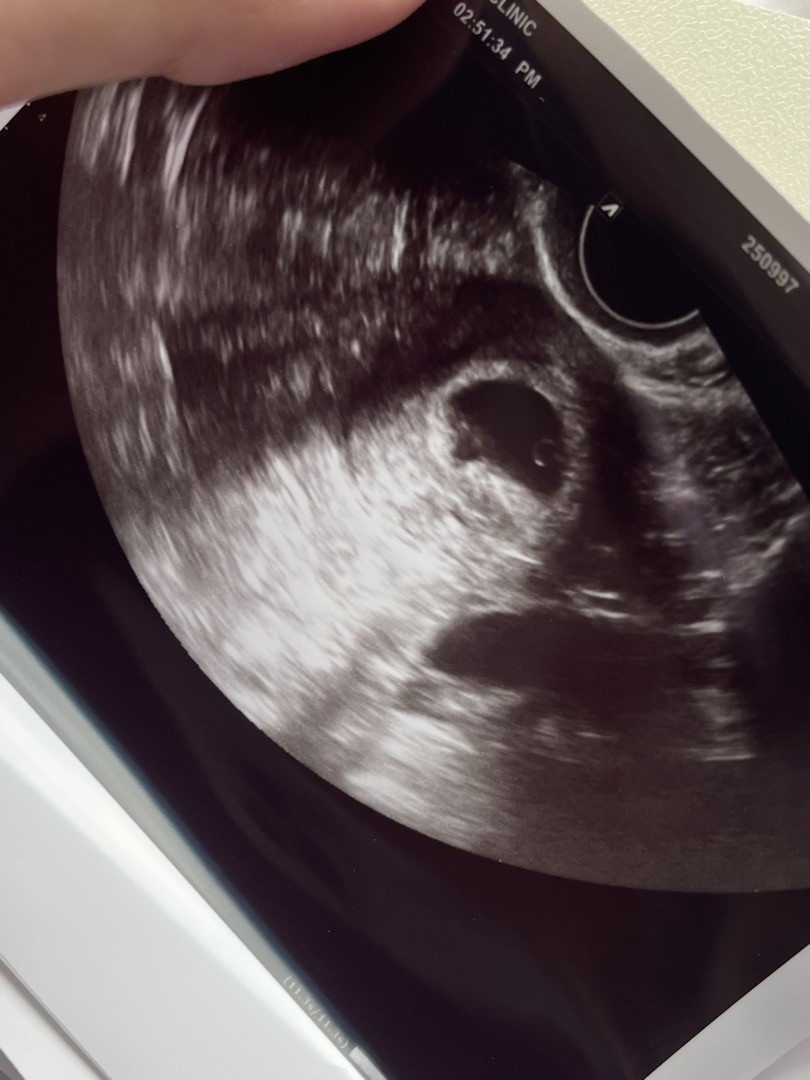

아기집 보구왔어요💍

너무 기여워요 ㅠㅠ 쩜이 아기라니... 사과씨 크기 너무 소듕해 오늘 아침에 갈색혈 비쳐서 놀래서 병원갔는데 별 의미 없는 혈일 가능성이 크다고 걱정하지 말라구 하셨어요 ㅠ